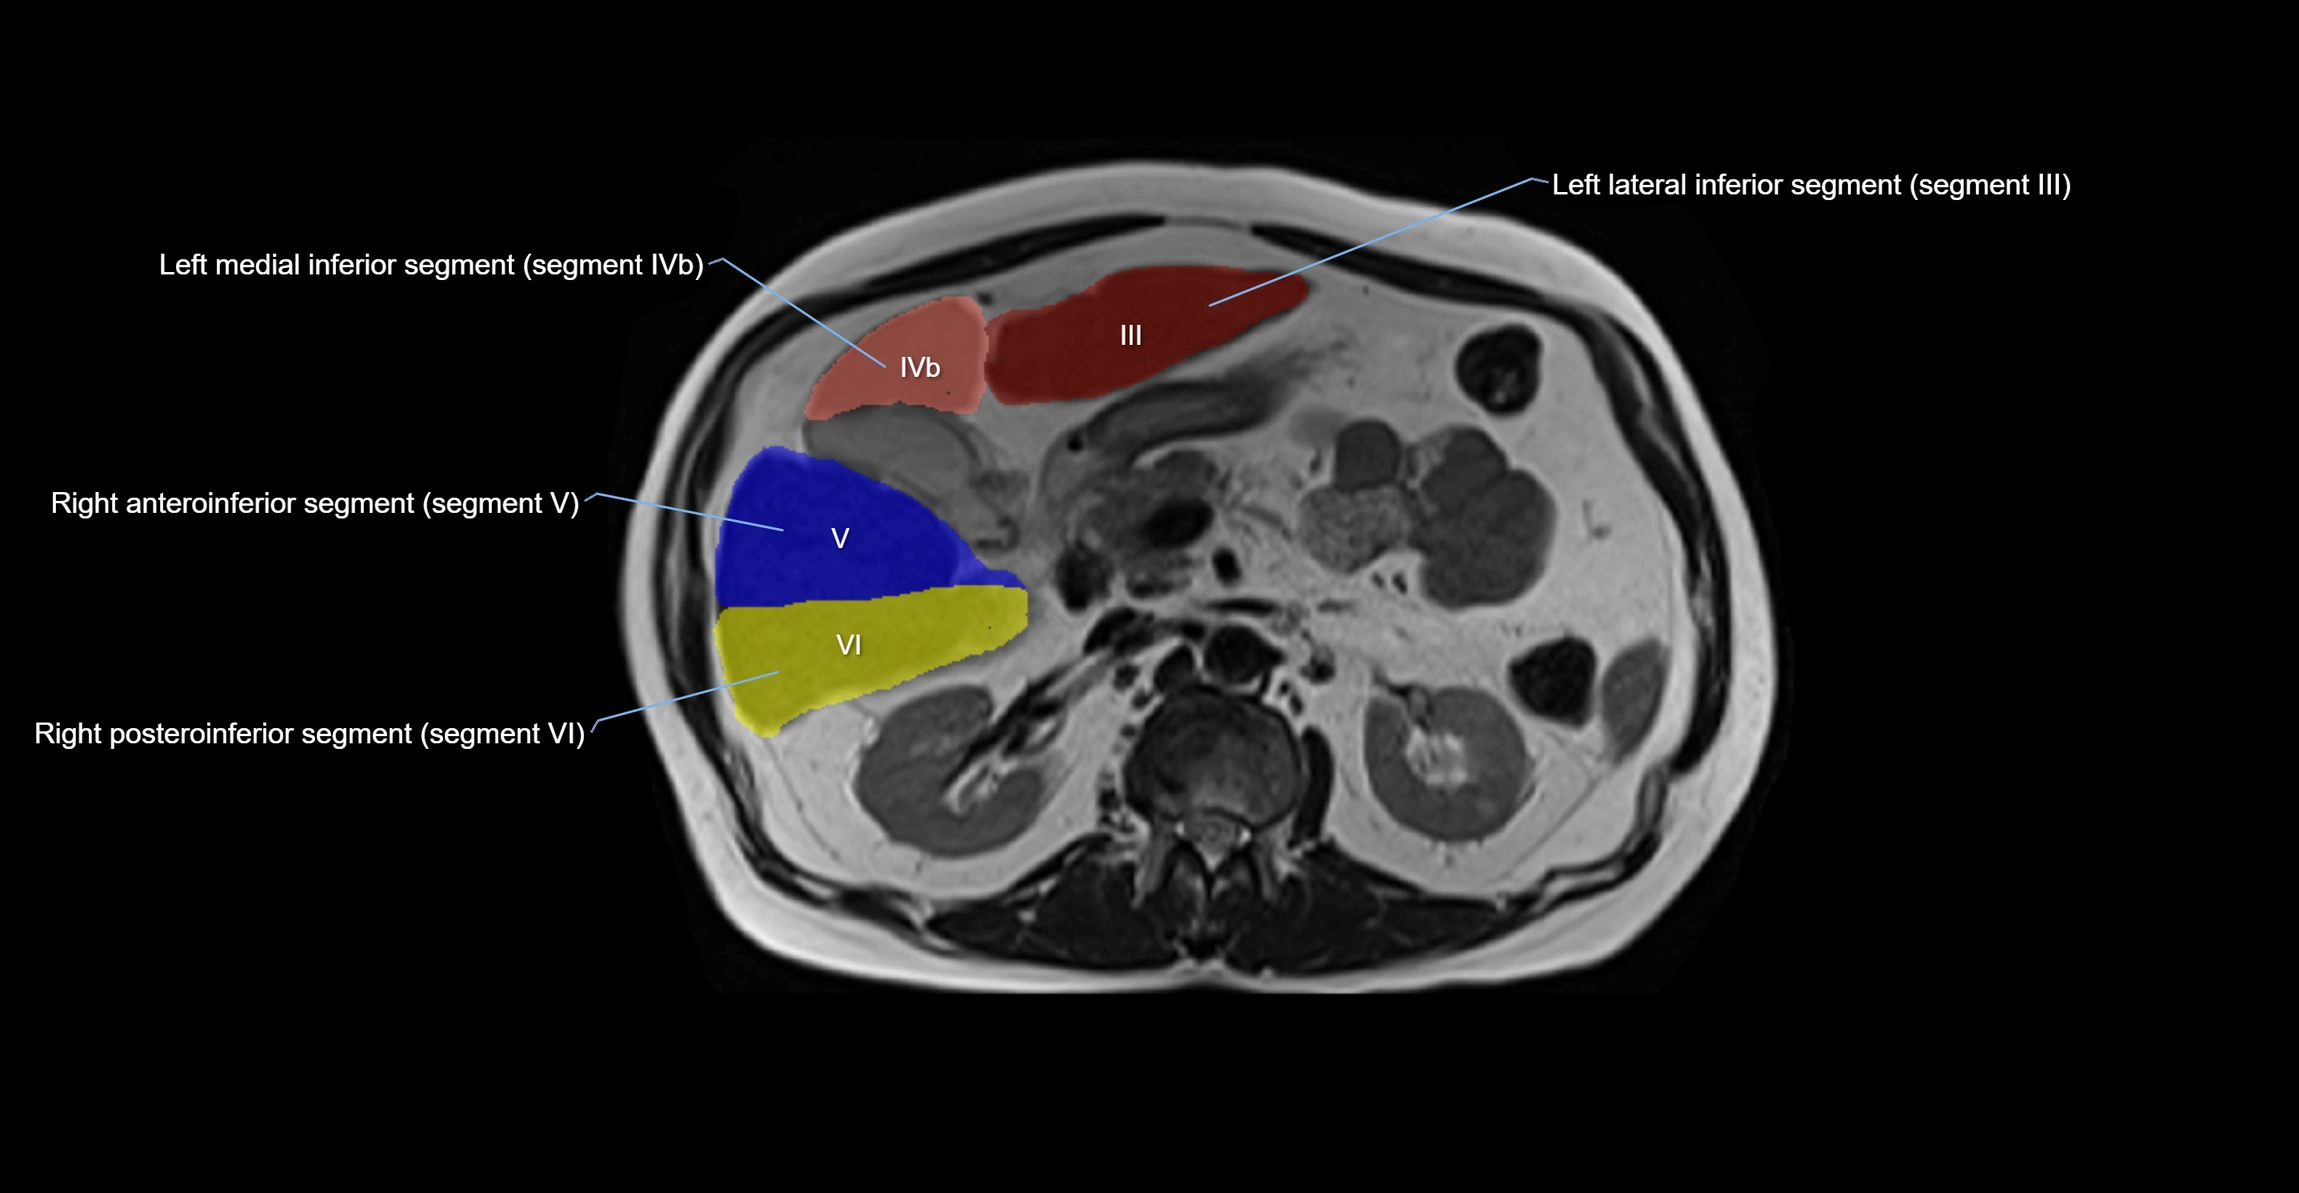

The caudate lobe of the liver is a distinct anatomical subdivision of the liver, designated as segment I in Couinaud’s classification. It lies on the posterior surface of the liver, between the fissure for the ligamentum venosum (left boundary) and the groove for the inferior vena cava (IVC) (right boundary). Superiorly, it is related to the posterior liver surface, and inferiorly it is separated from the left lobe by the porta hepatis.

The caudate lobe is unique because it receives dual portal venous and arterial inflow from both the right and left portal veins and hepatic arteries. It also has independent venous drainage directly into the IVC via multiple small hepatic veins, unlike other lobes that drain through the three main hepatic veins.

MRI image

image